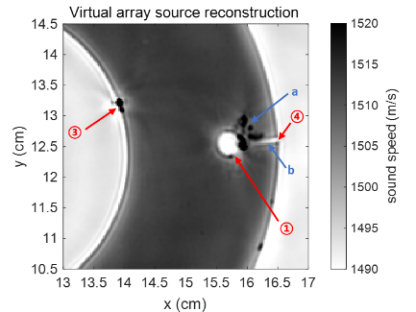

软组织体模的声速参数重建结果如图2所示,体模内外边缘清晰,尺寸和真实尺寸一致。一些已知特征也被成功重建,此外三点钟方向内部孔洞周围的一些破裂和小块脱落也在成像结果中清晰可见。该研究基于实验数据对软组织体模进行定量成像,分辨率可达亚毫米级。

图2 软组织体模声速重建结果(图/中国科学院声学研究所)